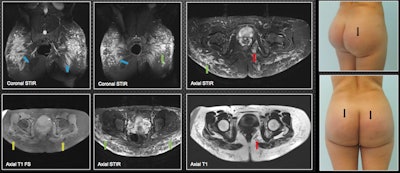

A 28-year-old patient was injected with biopolymers in the gluteal region seven years ago and now is experiencing inflammatory skin changes (blue arrows). MRI shows biopolymers located mainly in the subcutaneous cell tissue of the gluteal region, predominantly in the upper external quadrant in the form of vacuoles (green arrows). There is compromise of the gluteus maximus, where biopolymers are seen adopting a fusiform pattern at this level (blue arrows). There is migration to the left ischioanal fossa (red arrows). The yellow arrows show its hypointense behavior in T1-weighted fat-saturation sequences; the material has a hyperintense behavior in the short-tau inversion recovery sequences.MRI provides the most information to the radiologist and should be done on all patients, they stated. "It can warn the surgeon about the level of tissue compromise. It shows the affected planes and the approximate amount of biopolymers injected. It demonstrates their areas in the case of material migration."